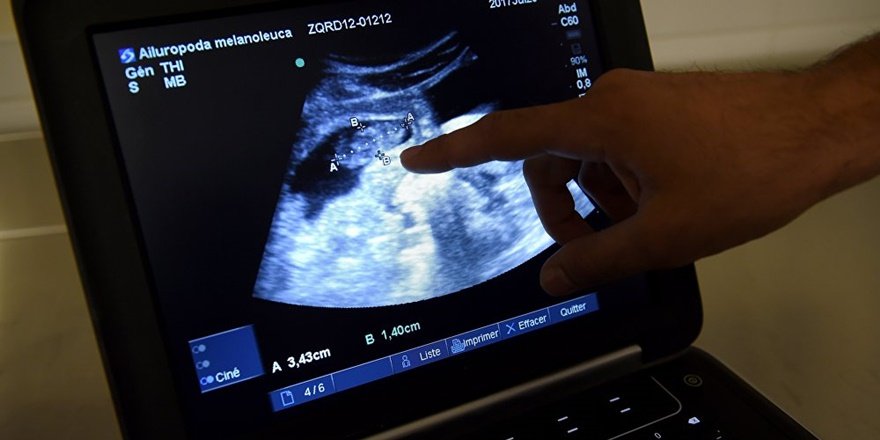

24 yaşındaki danielle davis 3. Artur carvalho nın özel bir klinikte rodrigo diye bilinen çocuğun annesine üç zorunlu ultrason yaptığı bildirildi. çin de küçük bir bebek gözleri olmadan dünyaya geldi. Gözsüz bebek görenleri hayrete düşürüyor.